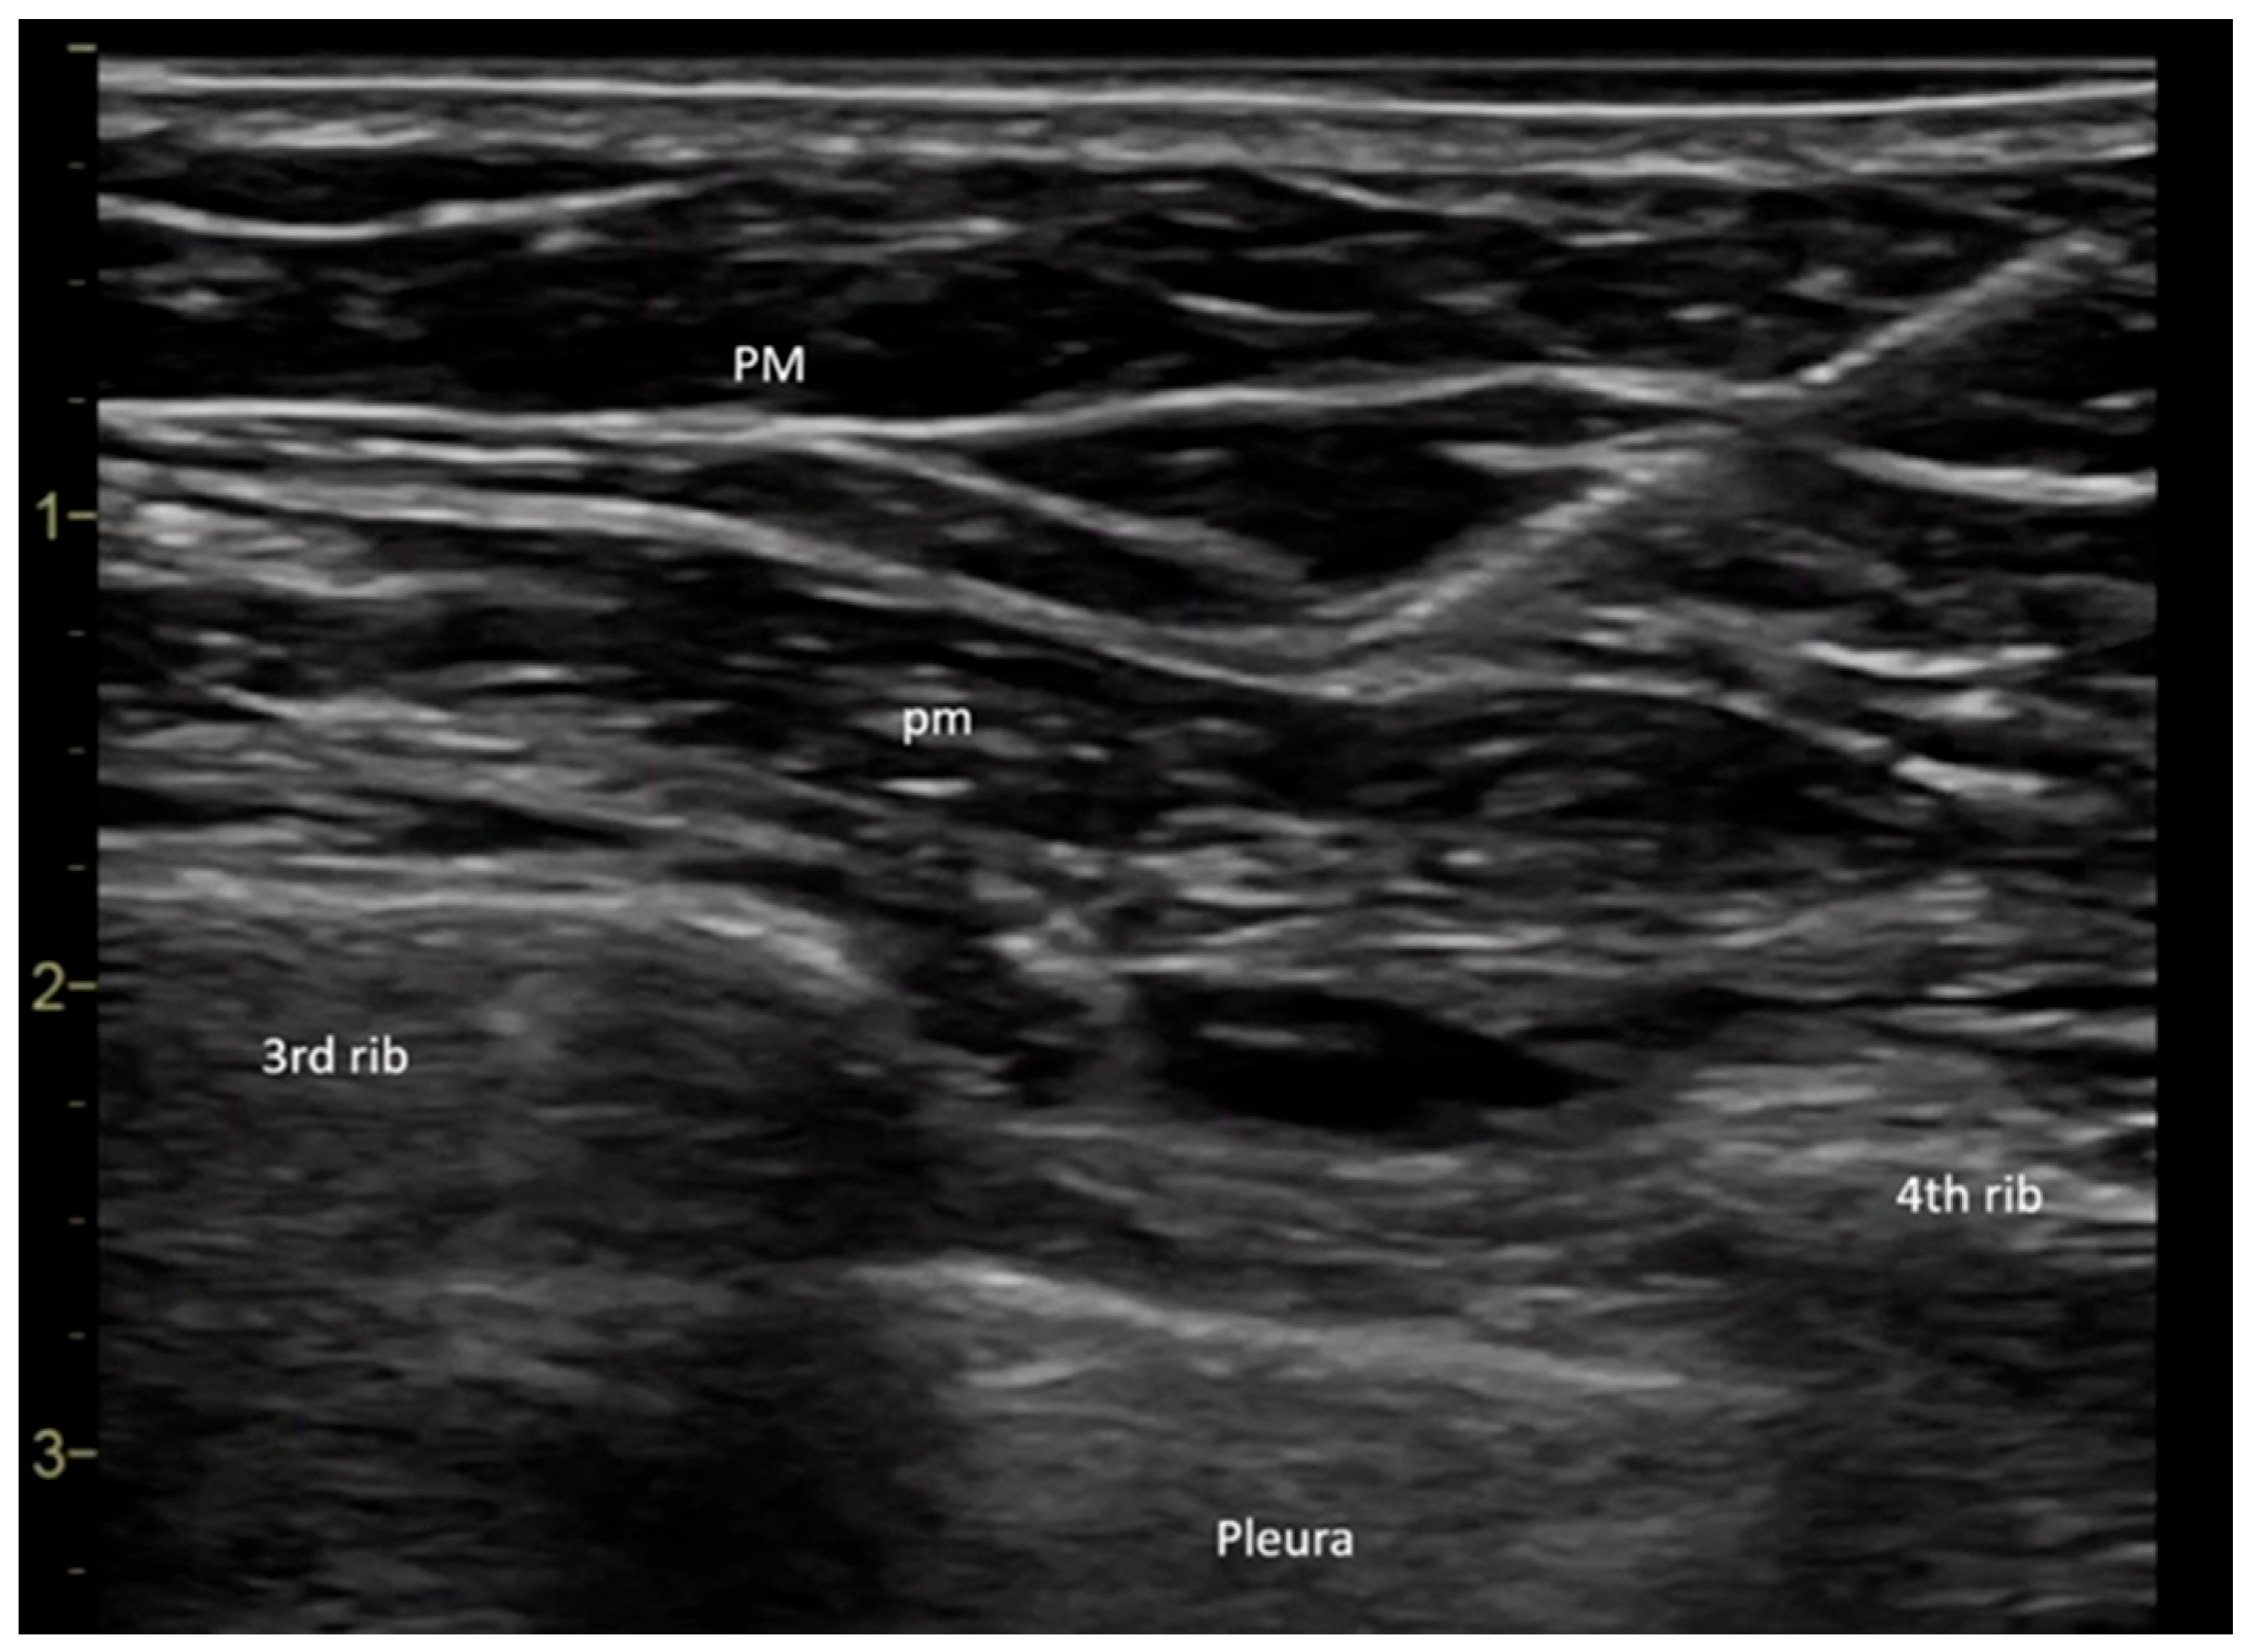

All procedures were performed in the operating room by the same anesthesiologist. Upon the patient’s arrival in the operating room, a peripheral intravenous line was placed, and baseline monitoring was initiated, including pulse, noninvasive blood pressure, and peripheral oxygen saturation measurements. The PECS II block was performed under ultrasound guidance using a General Electric Vivid I6 ultrasound system with an 8 L probe, with the patient positioned in the supine position and the arm placed alongside the body. The ultrasound probe was placed at the level of the coracoid process in the median parasagittal plane. The transducer was then slightly rotated laterally until it reached the deltopectoral groove, where the axillary artery was identified. To ensure the success of the block, it was crucial to locate the ribs. The rib immediately beneath the axillary artery was identified as the second rib. By translating the probe inferiorly and laterally, the third rib appeared in the ultrasound image, allowing for the evaluation of the fascial plane between the pectoral muscles. Before needle insertion through the skin tissue, 2 mL of a local anesthetic mixture was infiltrated using a 27 G needle to provide analgesia at the puncture site. A 20 G plexus needle (Pajunk Sonoplex—Geisingen, Germany 50 mm, 20 G diameter) was then used to puncture the cutaneous plane, with continuous visualization of the needle trajectory. The correct insertion of the plexus needle was confirmed by injecting a saline solution, which produced hydro dissection in the interpectoral plane. Further caudal and lateral translation of the probe allowed for the visualization of the fourth rib. At this point, the serratus anterior muscle could be observed in the ultrasound window. The fascial plane between the pectoralis minor and serratus anterior muscles was the target for the second injection (Figure 1) [13].

Figure 1. Ultrasonographic image showing the interfascial planes between the pectoralis major and minor muscles during local anesthetic injection (own archive). Legend: PM—pectoralis major muscle, pm—pectoralis minor muscle.